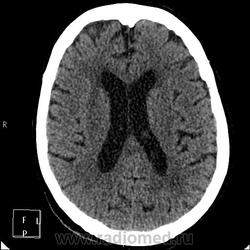

А контраст почему не делали? Больше похоже на тромбированные аневризмы

Неужели такие аневризмы? Бывает же! А сканы с контрастом есть?

Цифровых и плёночных доказательств на руках нет. Опухоль диагностирована в 2004 году, размером "с вишню", дебютировала птозом века правого глаза, умеренной головной болью в лобной области слева и постепенным снижением зрения, катаракта. Пациентка с трезвом уме и превосходной памяти (на мой субъективный взгляд))). В выписке результаты КТ, МРТ: неоперабельная опухоль селлярно-параселлярной области с прорастанием кавернозных синусов, аневризма сифона внутренних сонных артерий. Цитологию НЕ брали.

Не совсем понятно, опухоль + аневризма или как?

Да, опухоль, в толще которой аневризма сифона ВСА. Причем с обеих сторон.

Аневризмы с обеих сторон или опухоль?

И то, и другое. Доказать без контрастирования не могу. Когда сама впервые увидела, анамнеза не знала, подумала о двусторонней аневризме. И не угадала.

Насчет опухоли у меня большие сомнения. То что седло растянуто, еще не показатель. Седло увеличивается в размерах даже при гипертонии,а тут такие аневризмы. Самой опухоли не видно, в просвете турецкого седла медиальные полюса аневризм. Ну впрочем не так это важно, интерес чисто теоретический, да и верификации видимо не будет. Спасибо большое за демонстрацию.

Случай-таки не верифицированный. Сочетание опухоли с аневрзмами - это очень странно. Боюсь, тут какая-то путаница.